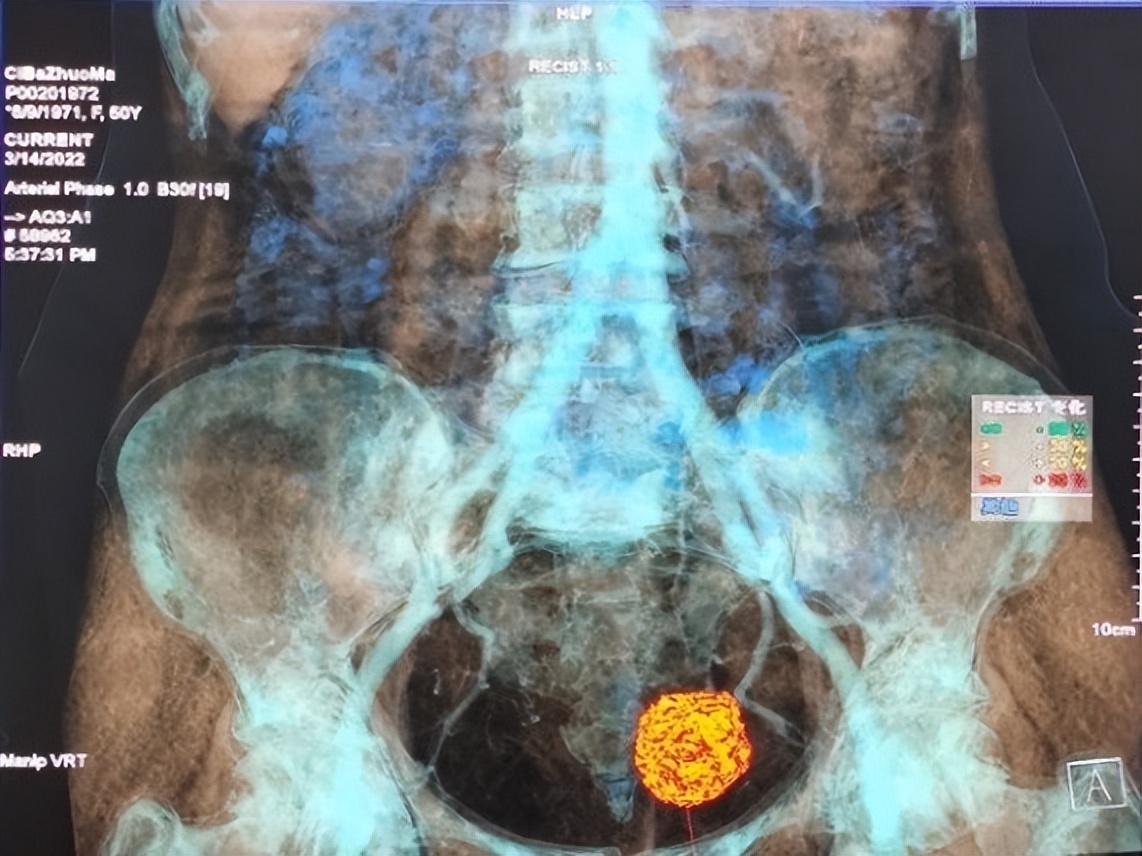

去年10月下旬,一位战士突发急性胸痛,在高压注射器配置不到位的情况下,他紧急为患者进行了手动注药的CT增强扫描,确诊了第一例A型主动脉夹层,实现了阿里高原上CT增强扫描“零”的突破。随着关键配件的到位,放射科逐步开展了40余例CT增强检查,包括肿瘤的多期动态CT增强、冠状动脉CT造影、头胸腹部血管CT成像、泌尿系CT造影(CTU)、胸痛三联CTA等。